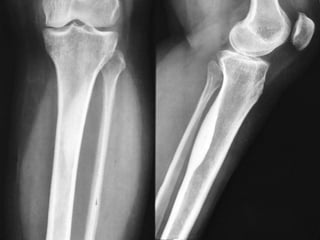

• Any bone can be involved,

• There is a predilection for the lower extremity,

with half the cases involving the femur or

tibia.

• The tumor may be found in cortical or

cancellous bone, producing a distinct x-ray

appearance of cortical sclerosis.

Osteoid Osteoma • Anybone can be involved, • There is a predilection for the lower extremity, with half the cases involving the femur or tibia. • The tumor may be found in cortical or cancellous bone, producing a distinct x-ray appearance of cortical sclerosis. • 5% of tumors are subperiosteal.

Osteoid Osteoma • CTmay detect the nidus, whereas roentgenograms show only sclerosis.